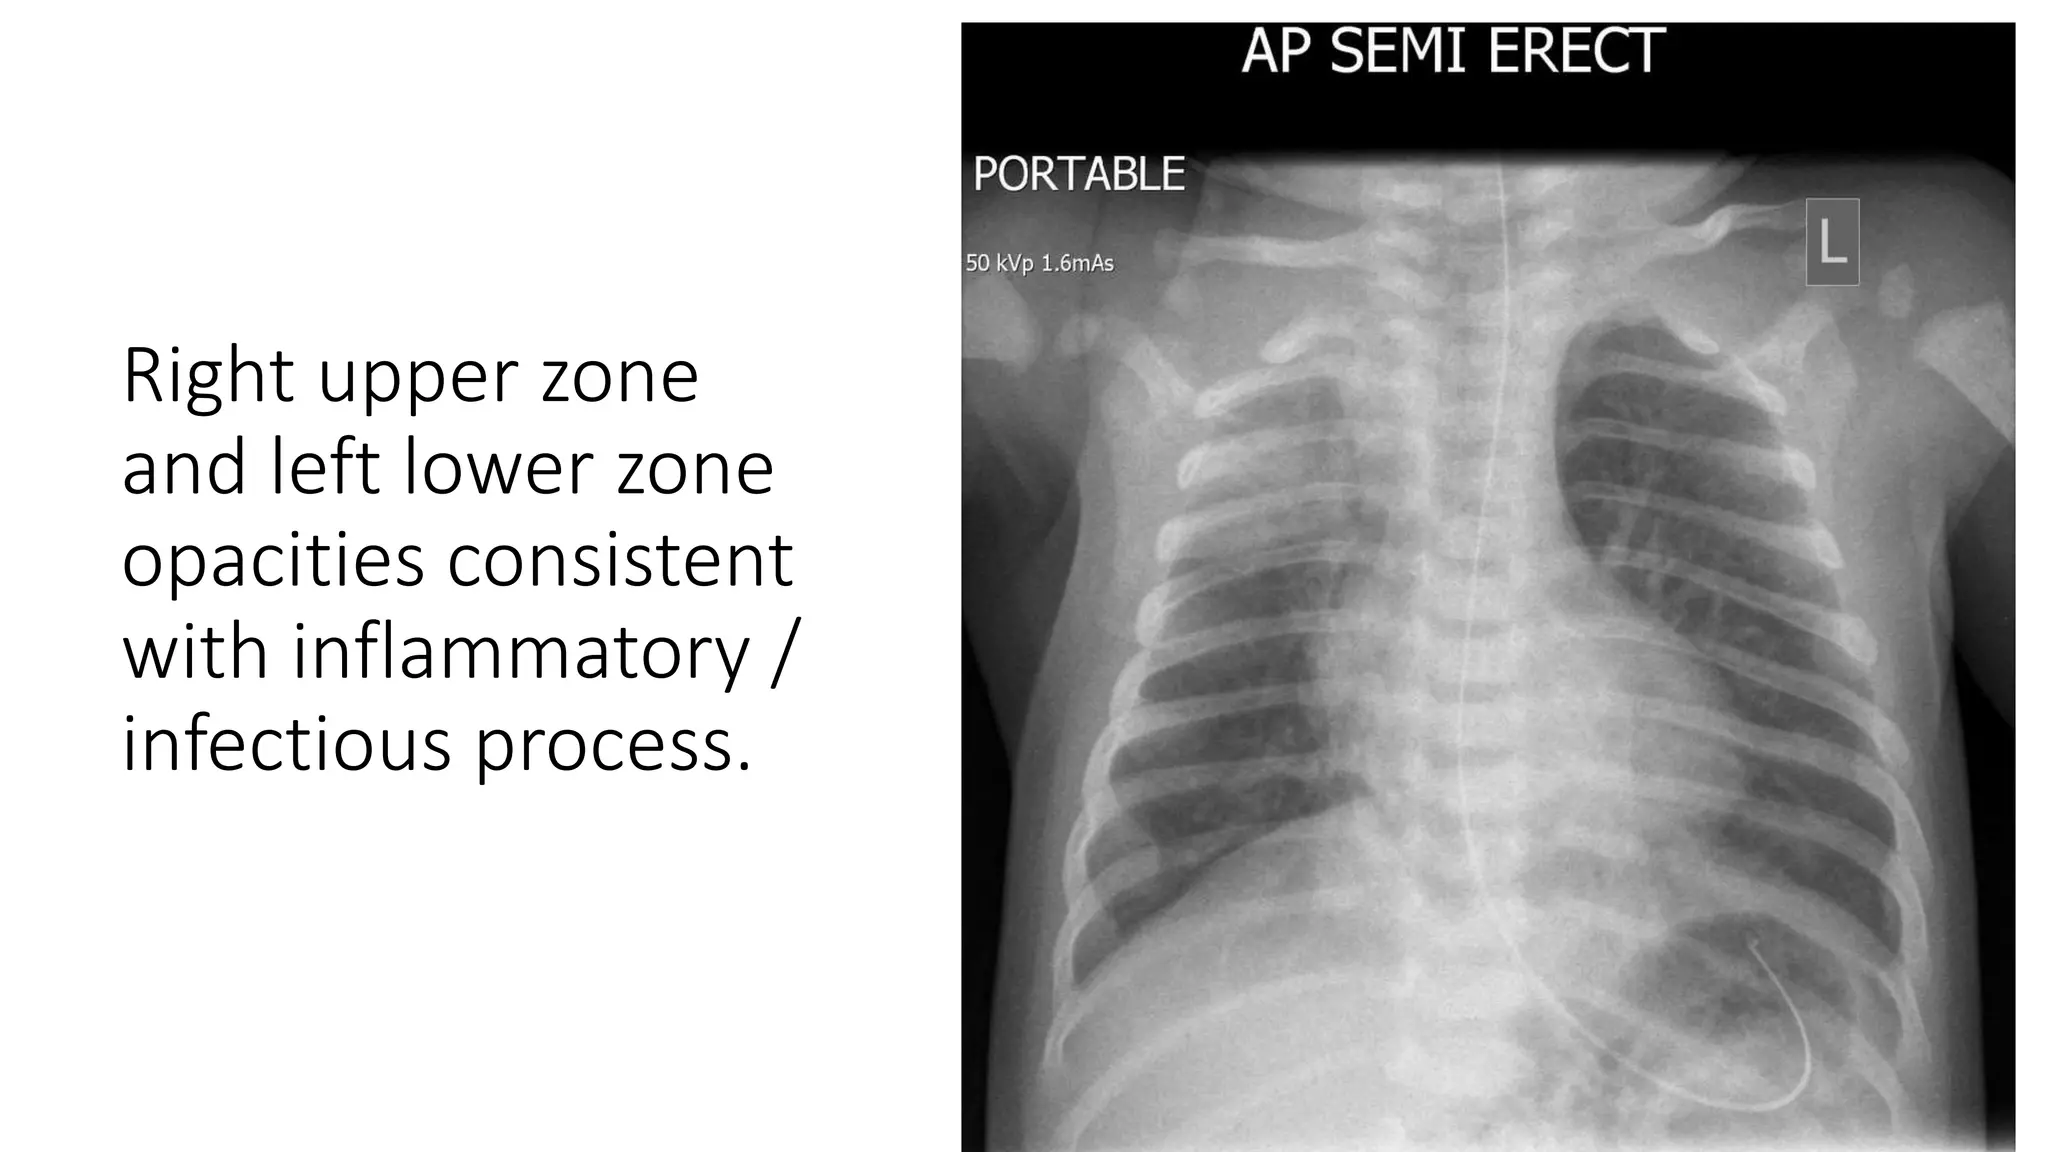

This document provides an overview of neonatal chest x-rays, including when they should and should not be performed, what a normal x-ray looks like, common positions of tubes and catheters, and common causes of respiratory distress in neonates. It discusses the appearance of a normal chest x-ray as well as conditions like respiratory distress syndrome, transient tachypnea of the newborn, meconium aspiration syndrome, and pneumonia. Surgical conditions like diaphragmatic hernia and esophageal atresia are also reviewed.